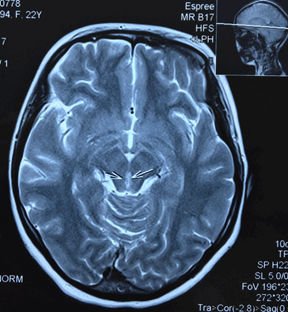

Пациентка направляется на МРТ головного мозга без контрастирования с подозрением на синдром Вернике и образование ГМ (рис.).

МРТ головного мозга без контрастирования пациентки Ч. Поражение вещества мозга по ходу паравентрикулярных отделов варолиева моста, водопровода и медиальных отделов таламуса

Результаты МРТ головного мозга пациентки: «Топография срединных структур мозга не изменена. Обращает внимание поражение вещества мозга по ходу паравентрикулярных отделов варолиева моста, водопровода и медиальных отделов таламуса. В белом веществе лобно-теменных долей с обеих сторон определяются очаги лейкопатии. Мозолистое тело, гипоталамо-гипофизарная область, продолговатый мозг и мозжечок без особенностей. Область мостомозжечковых углов без патологических изменений. Желудочковая система мозга не расширена и не деформирована. Конвекситальные субарахноидальные пространства и базальные цистерны мозга не расширены. Соотношения в краниовертебральном переходе не нарушены. На скрининговой МР-ангиографии Виллизиева круга признаков артериовенозной мальформации и аневризм сосудов головного мозга не выявлены. Заключение: МР-признаки энцефалопатии Вернике. Очаги лейкопатии в белом веществе лобно-теменных долей с обеих сторон, вероятно, как проявление резидуальной энцефалопатии».